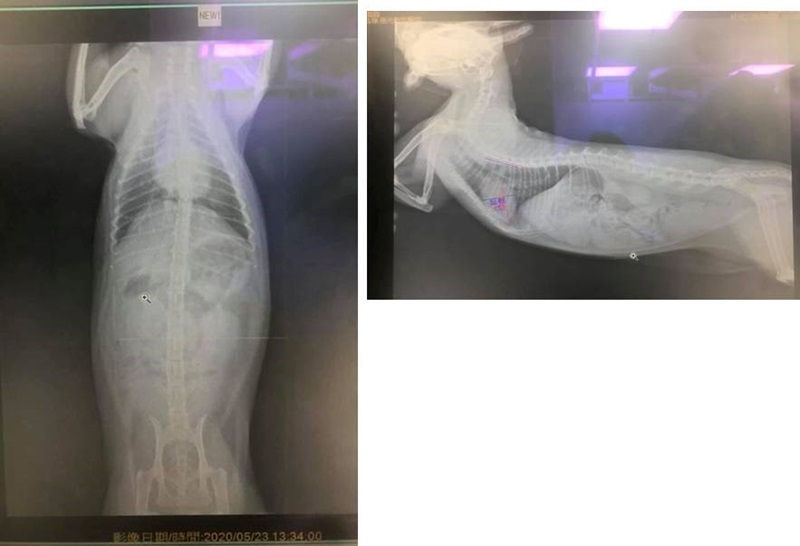

2020年5月間,照護員發現踏踏看來精神較不好,進食情況也有變差,安排約診檢查,醫師進行血檢及X光檢查,血檢結果,肝、腎、紅白血球指數、心臟快篩檢驗都正常,X光影像雖然心臟稍大一些但也沒有特別異常,但眼睛有些分泌物,及發炎指數高一些,研判可能是上呼吸道的問題讓踏踏不舒服,因體重未掉,醫師認為可以先點眼藥水、再觀察看看。

本筆醫助是踏踏於2020年5月23日至極光醫院看診的費用,包含抽血檢驗、X光檢查、用藥,請大家幫忙可愛的踏踏,謝謝。

踏踏近期精神食慾較差而約診,外觀檢查,眼睛分泌物較多,無流口水,X光檢查,除心臟看來稍微大一些,其他無發現異常,血檢結果,肝、腎、紅白血球指數、心臟快篩檢驗都正常,只發炎指數較高(5.5,正常值2.8-5.1),醫師認為發炎指數高及食慾精神變差,應是與眼睛分泌物多有關,但檢查沒有其他異常,今天體重也沒問題,所以先再觀察,原本用藥照舊,及早晚點眼藥水點一週。